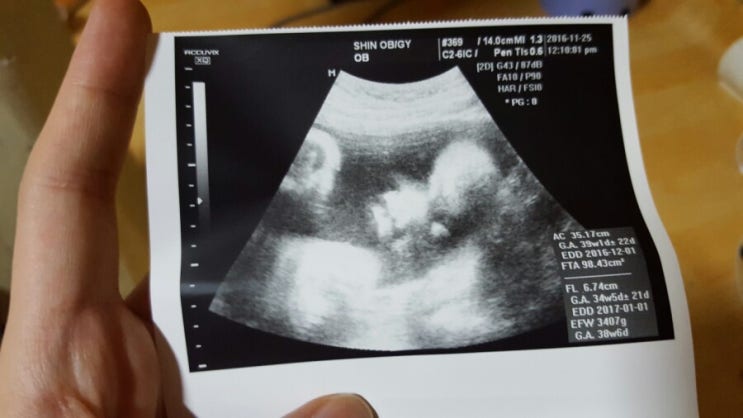

초음파 사진 찍을때부터 머리숱이 많다는걸 알았지만, 정말 머리숱이 많고 까만머리칼인 울아가완전 장발 ...